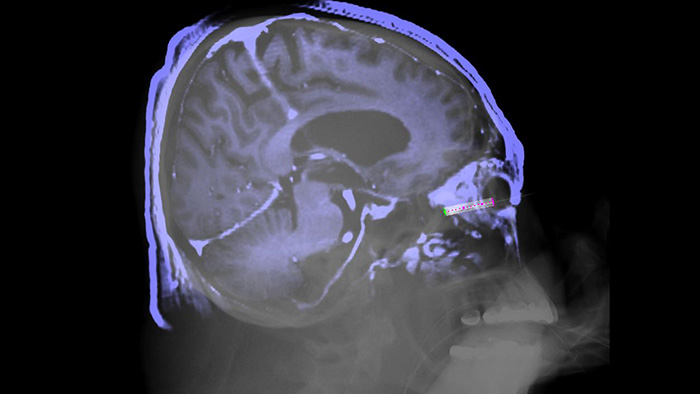

SmartCT Soft Tissue ofrece una técnica de adquisición de tomografía de haz cónico (THC) aumentada con guía paso a paso, visualización 3D avanzada y herramientas de medición, todo accesible en el módulo de pantalla táctil desde la mesa. Para ayudarle a adquirir imágenes de THC correctas a la primera y agilizar su flujo de trabajo, se le guía a través de los pasos clave.